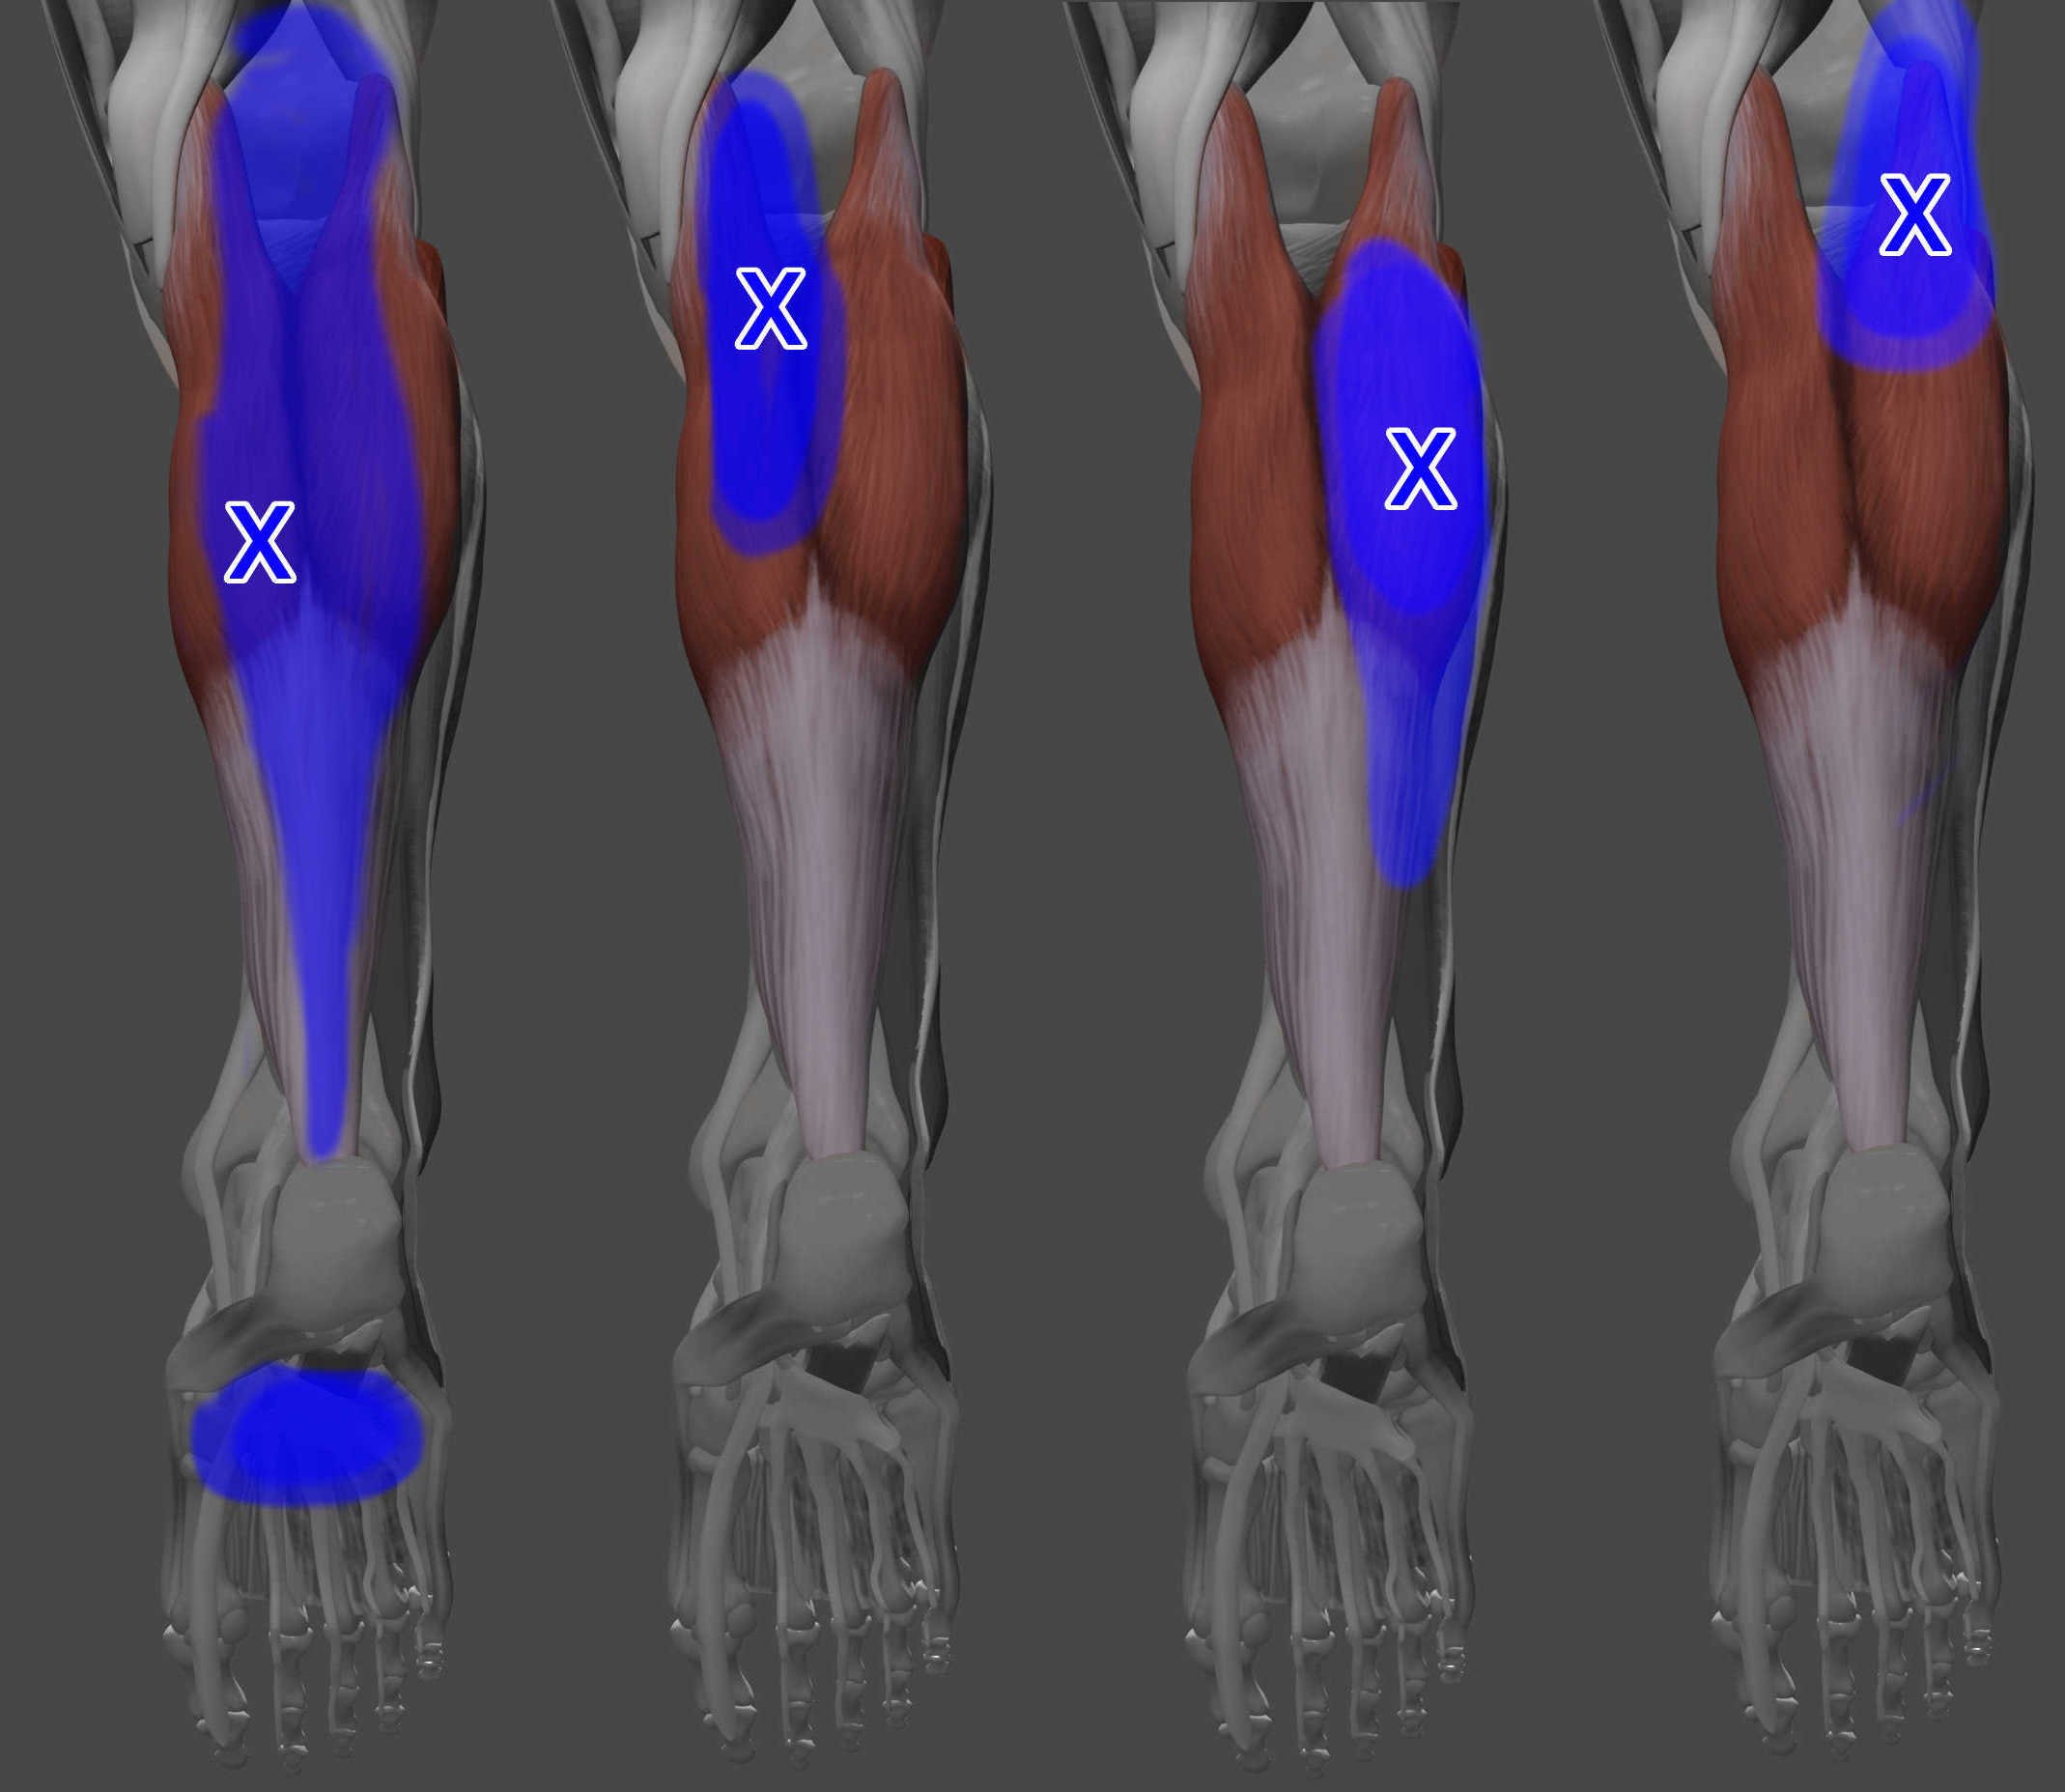

Acupuncture for Calf Trigger Points

The calf muscles are made up of the gastrocnemius and soleus muscles. Calf trigger points can cause posterior lower leg pain, knee pain, and heel pain. They can mimic symptoms of more serious conditions like Achilles tendonitis, plantar fasciitis, and Baker’s cysts. Learn more about the calf muscles, how trigger points form in them, and how acupuncture and dry needling can relieve pain and restore range of motion in the calf and lower leg.